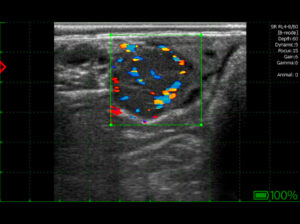

Le premier et le plus fréquent signe d’acyclicité est la chaleur silencieuse. À la palpation et à l’échographie, les ovaires sont petits, flasques, lisses et dépourvus de structures fonctionnelles telles que le corps jaune (CJ) et les follicules (F). L’inactivité ovarienne se traduit par l’incapacité de produire des quantités adéquates d’hormones, à savoir les œstrogènes et la progestérone, qui sont essentielles pour un cycle normal et une insémination efficace.

Figure 1 Dysfonctionnement ovarien – absence de structures (image diagnostique prise avec l’échographe iScan 3)